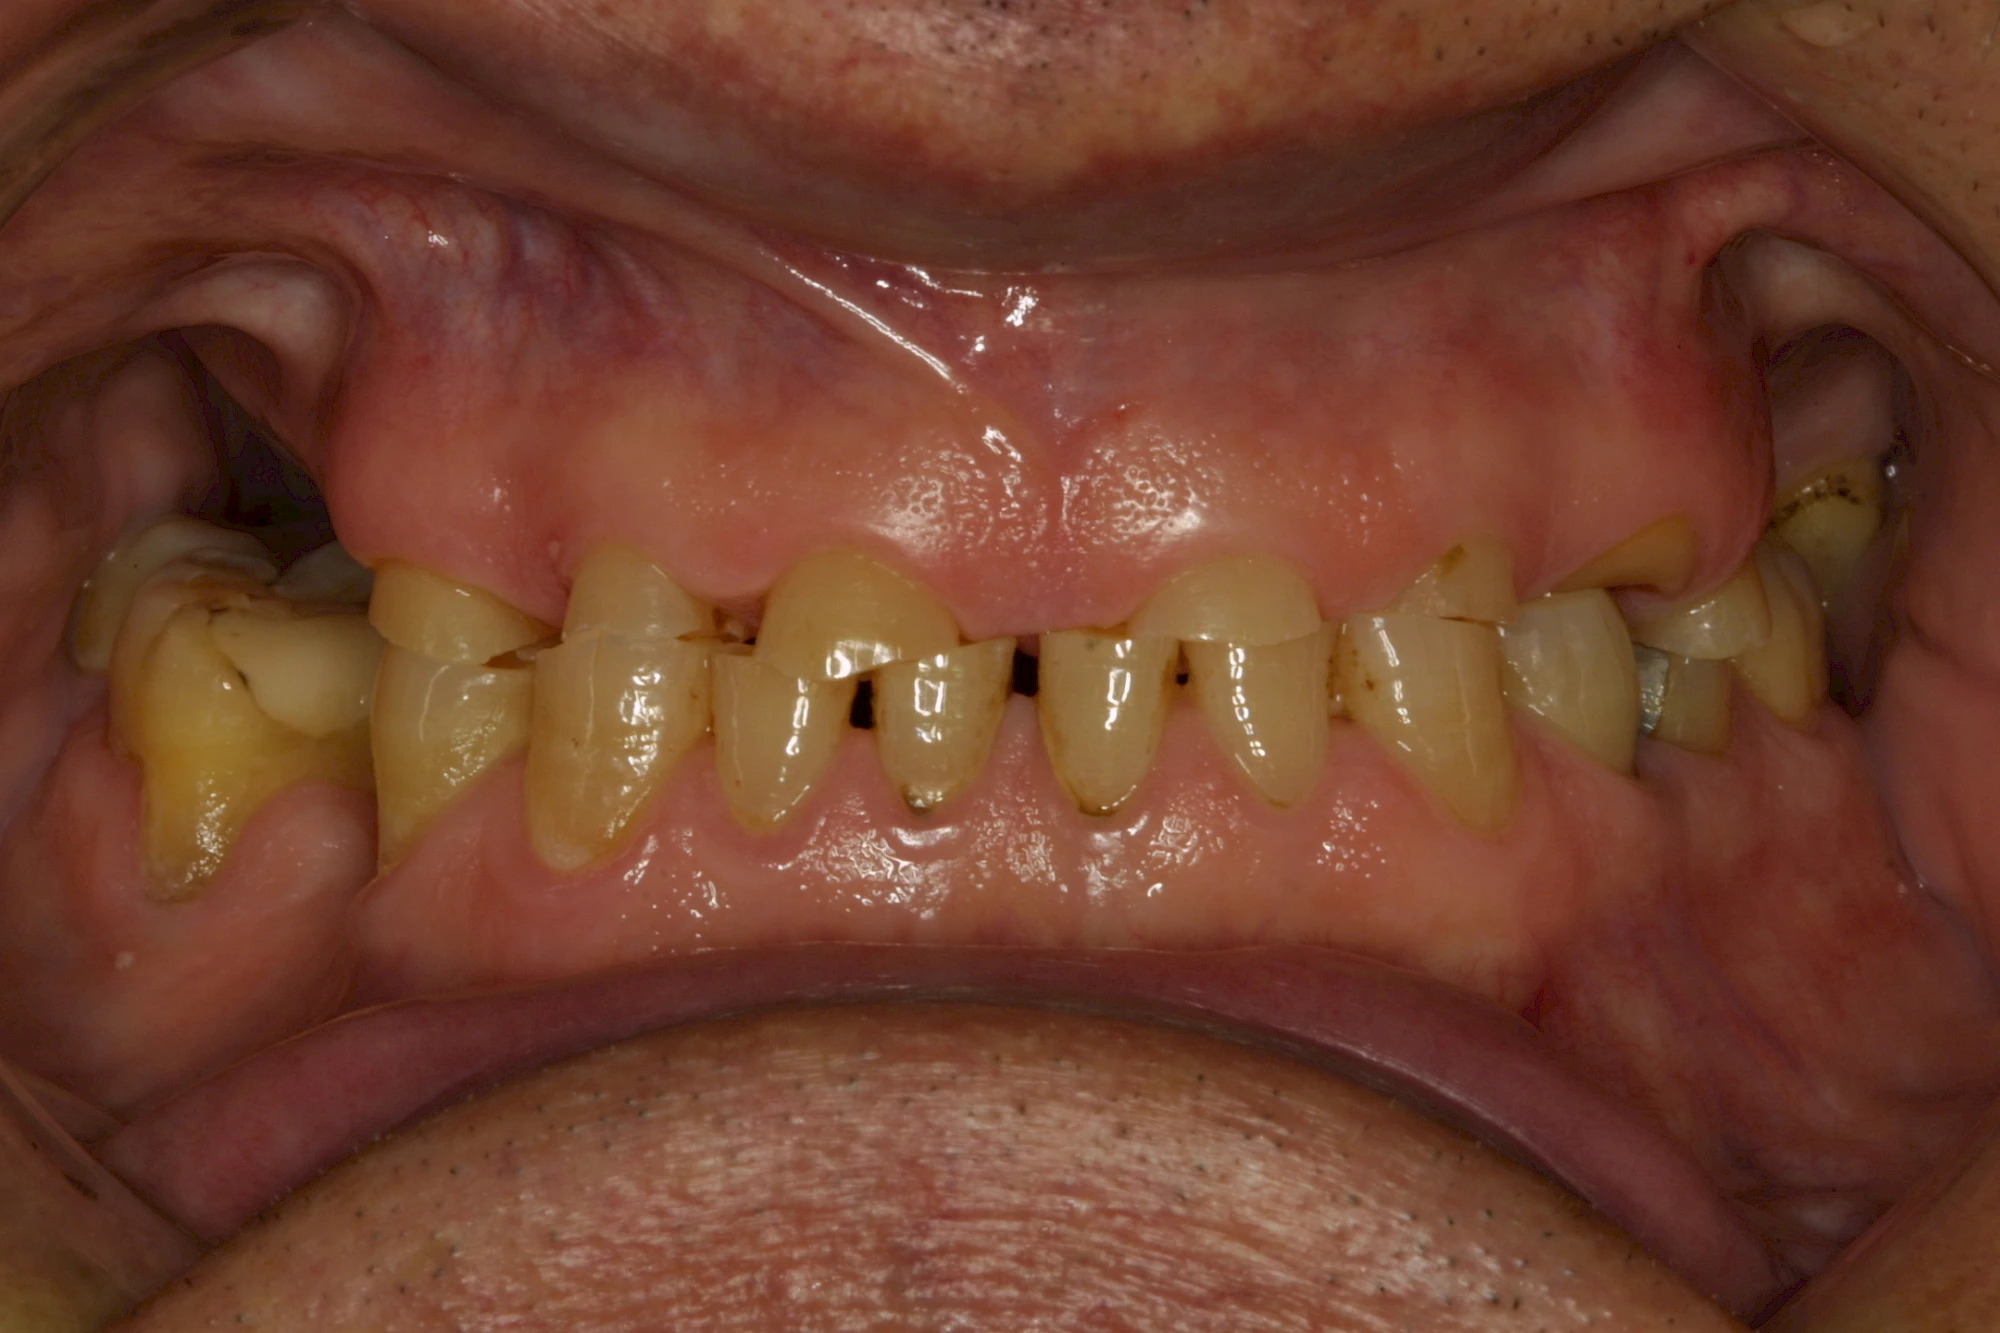

Über die Zeit können verschiedene Prozesse die Zahnhartsubstanzen aufzehren:

- Abnutzung durch Kauen (Abrasion) oder duch durch übermäßiges Knirschen bzw. Pressen (Attrition)

- Säurebedingte Auswaschung (Erosion)

- Knirschen bzw. Pressen und ungünstige Putztechnik (Druck): keilförmige Defekte

Die Zähne können dabei auf Reize (warm, kalt, süß, sauer) oder auch beim Zähneputzen empfindlich oder schmerzhaft sein. In allen diesen Fällen ist es sinnvoll, den Zahnarzt zu kontaktieren und das weitere Vorgehen abzustimmen.